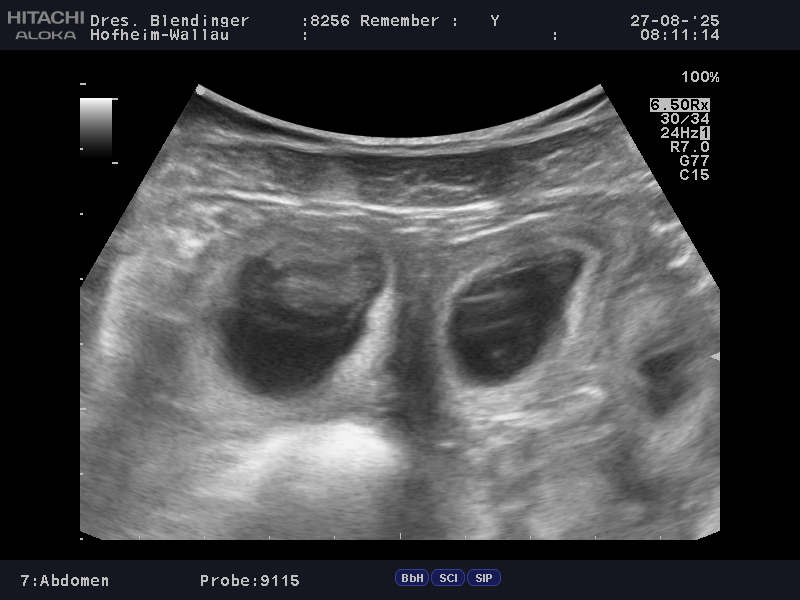

Nach dem positiven Ultraschallbefund heute ist es amtlich… Unser Mädel ist trächtig !!! Remember hat damit gezeigt, dass sie sich doch in die erfolgreichen fruchtbaren Ahnen (mütterlich) einreihen kann. Die Tierärztin konnte 6-8 Fruchtblasen erkennen.